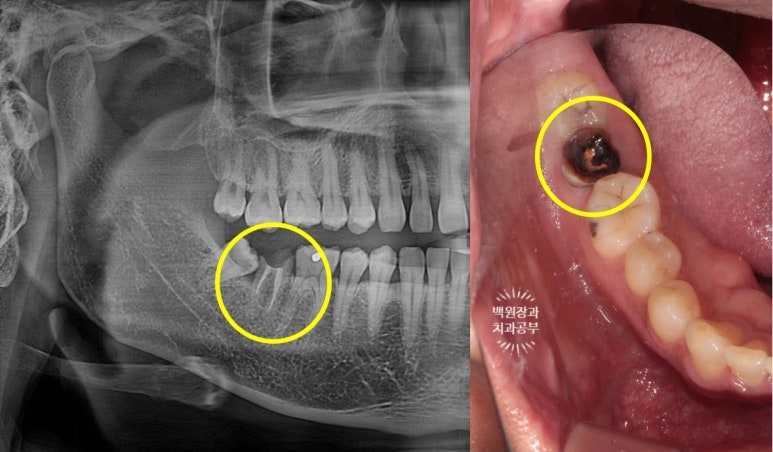

노란색으로 동그랗게 표시해놓은 치아가 오른쪽 아래 두번째 큰어금니입니다.

오른쪽 사진을 보시면, 분홍색 재료가 신경치료 때 쓰이는 재료인데 모두 드러나 있어요.

어쩔 수 없이 빼야하는 상황입니다.